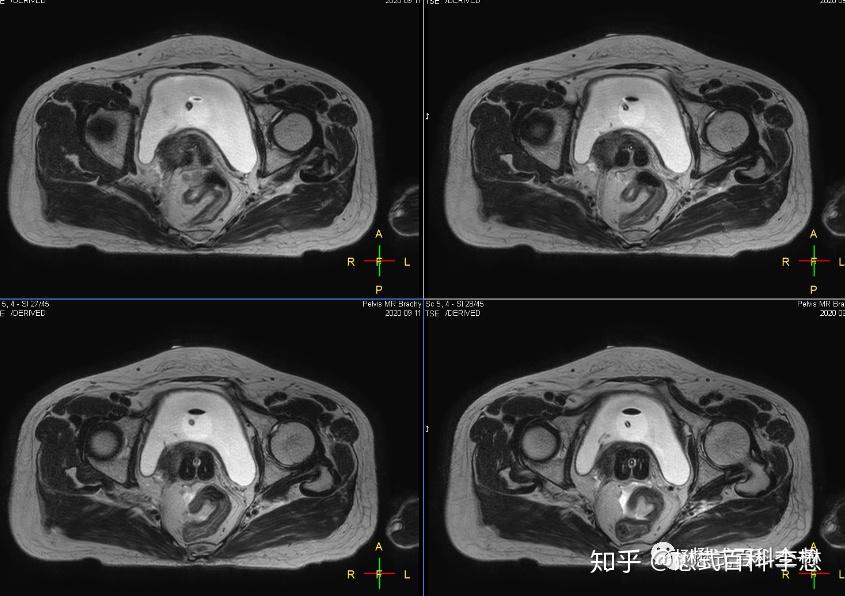

图8:t2wi显示施源器位置图9,10:mdixon脂肪抑制图像必要时候可以行